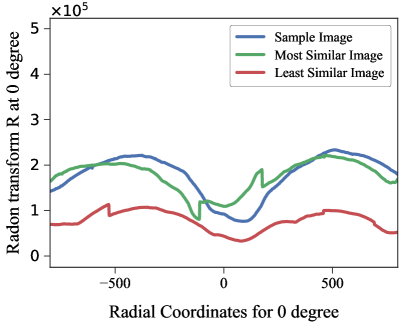

7.1.1 Using Radon Transform and Bhattacharyya Distance to find visually similar images

We use the publicly available chest x-ray dataset (JSRT) [20] with reference boundaries given in the SCR dataset [21]. For a given test image, the radon transform of that image is calculated at radial coordinates, ranging from 0 to 90 degree. The radon function computes projections of an image along specified directions. Bhattacharyya distance [34] is calculated between radon transform of test CXR and the sample CXRs to find 5 visually similar samples from the JSRT dataset. We use the most similar images from the dataset to register to the test image. As mentioned by Candemir et al. [5], the main objective of similarity measurement is to increase the correspondence performance and reduce the computational cost during registration.